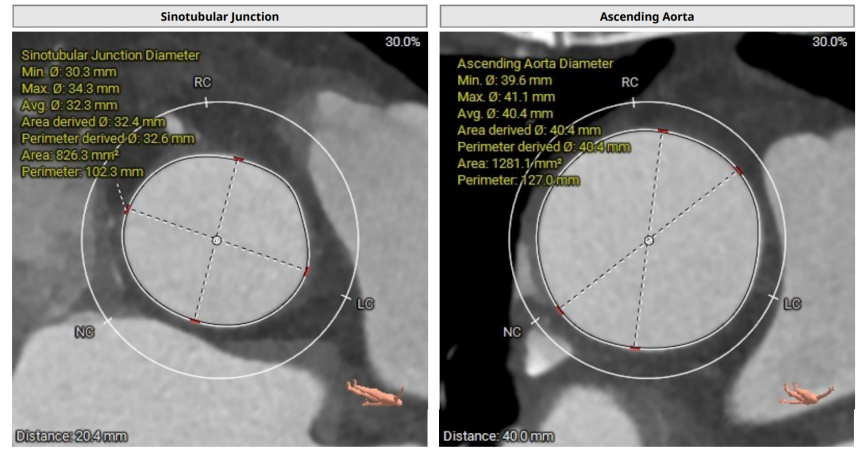

术前CT

术前CT(上下滑动查看更多图片)